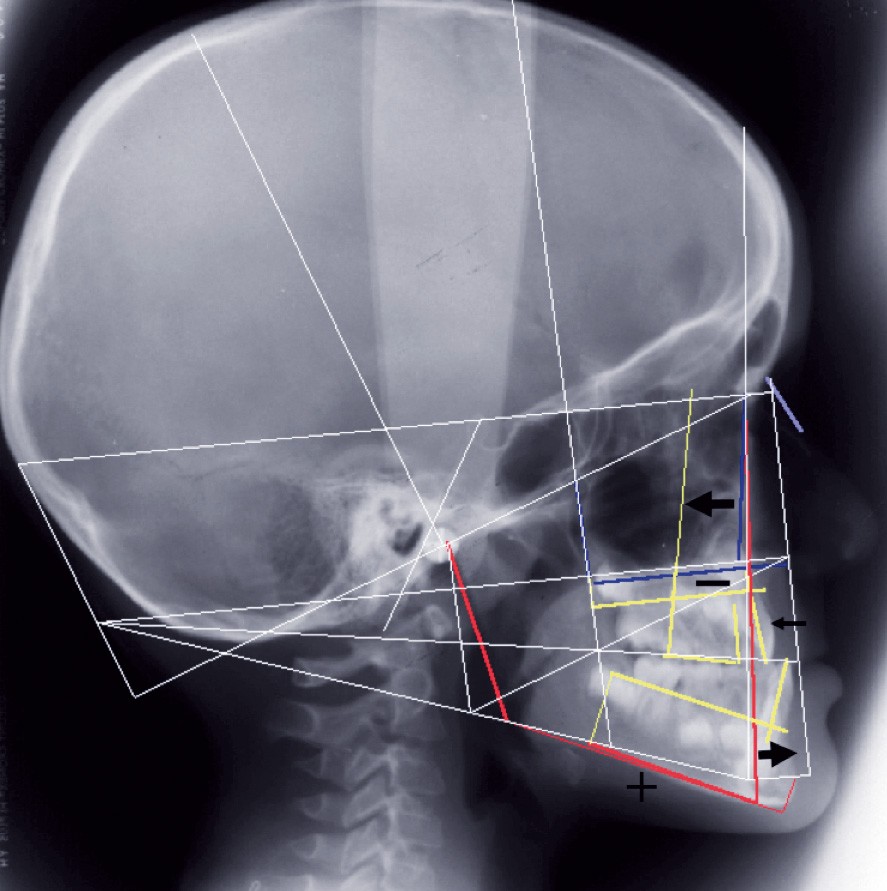

Le bilan radiographique (fig. 6) par l’analyse architecturale de Delaire et l’analyse dento-squelettique confirme l’examen clinique et conduit au diagnostic radiologique suivant :

• pas de prédisposition de la base du crâne à la classe III,

• rétromaxillie,

• brachymaxillie avec petite brachyprémaxillie,

• linguoversion incisive maxillaire,

• légère prognathie mandibulaire par dolichocorpie.